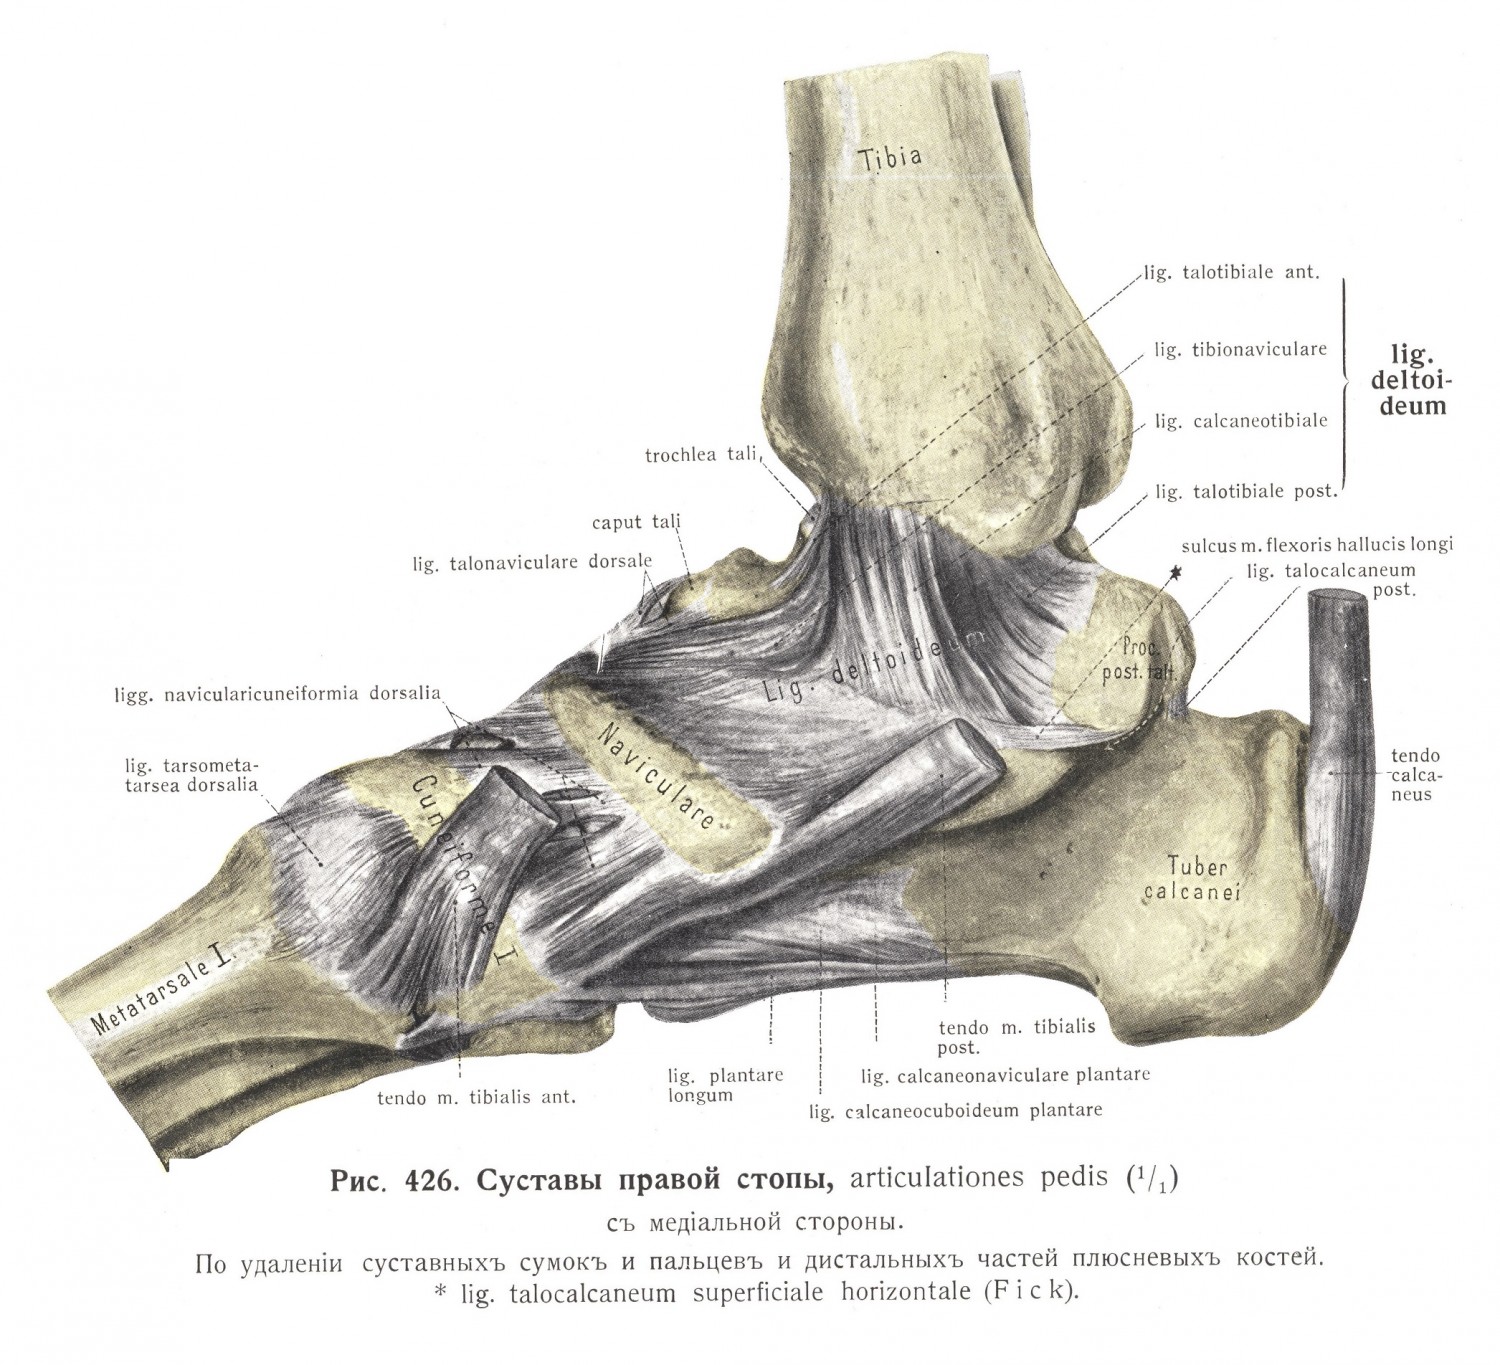

Анатомические фото голеностопного сустава и его суставных поверхностей